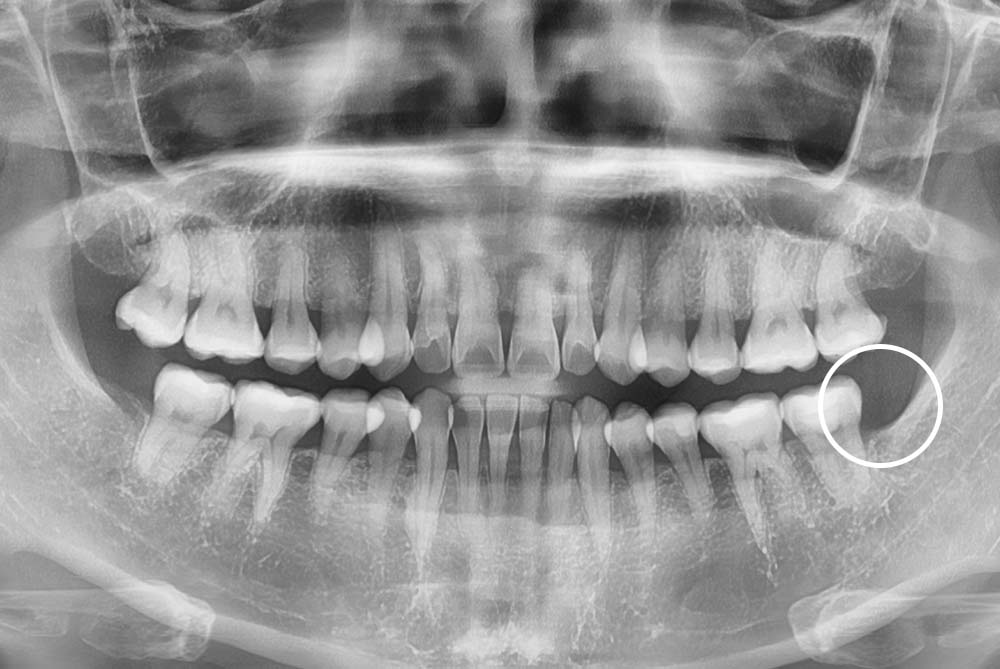

[사랑니] 매복 사랑니 발치

치료후 : 2022-05-26

세종치과는 구강악안면외과학 박사이신 원장님이 발치하는 치과입니다.